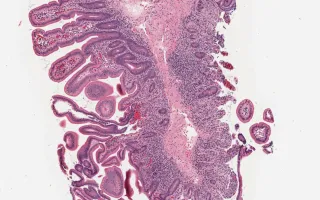

Autoimmune enteropathy is a rare cause of intractable diarrhea. The childhood form is often associated with IPEX (immunodysregulation, polyendocrinopathy, enteropathy, X-linked) syndrome and APECED (autoimmune polyendocrinopathy, mucocutaneous candidiasis, and ectodermal dystrophy) syndrome. The typical histological findings are villous atrophy, an increase in lamina propria inflammation, an increase in intraepithelial lymphocytes (IELs) (primarily at the base of crypts), an increase in apoptotic bodies, and occasionally a lack of goblet cells, Paneth cells and/or endocrine cells. In small intestinal biopsy, note the absence of goblet cells and Paneth cells. The villous architecture here was preserved with no IELs. In the large intestine, there was absence of goblet cells, active inflammation with increased basal crypt IELs and prominent basal crypt apoptoses. The FOXP3 immunostain shows the presence of T-regulatory cells thus excluding IPEX syndrome. The presence of enteroendocrine cells was confirmed by synaptophysin and chromogranin which helped to rule out a stem-cell related lack of development.

This slide shows H&E stain of the small intestine. See Related Content for H&E stain of large intestine and FOXP3 stain.